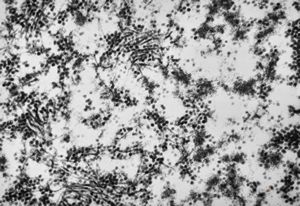

M,10y. | herpetic encephalitis